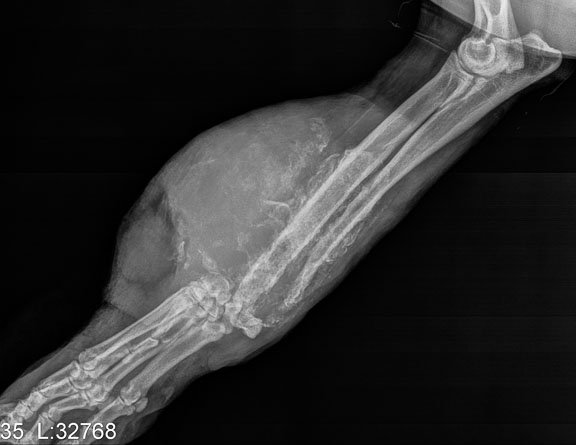

Cancer